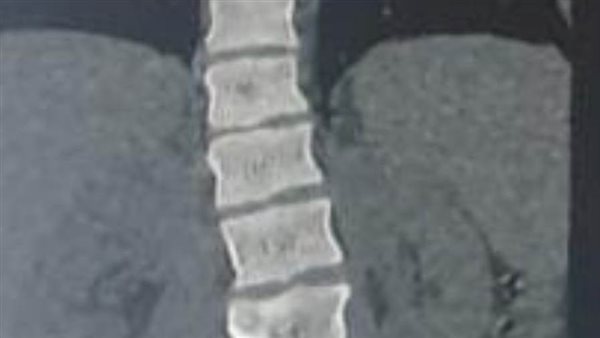

وأضاف مدكور أنه جرى استقبال المريض وهو يعاني من آلام شديدة بالظهر، مع عدم الاستجابه للعلاج الدوائي والعلاج الطبيعي، وعقب الفحص تبين وجود اعوجاج بالفقرات الصدرية والقطنية بالعمود الفقري.

فيما أوضح الدكتور احمد البيلي، وكيل المديرية للطب العلاجي، أنه عقب مناظرة الأشعة والفحوصات، تم إجراء العملية التي استغرقت 4 ساعات كاملة لإصلاح الاعوجاج، بواسطه تثبيت الفقرات الصدرية والقطنية واستعدال العمود الفقري، وخروج المريض من المستشفى وتحسن حالته.